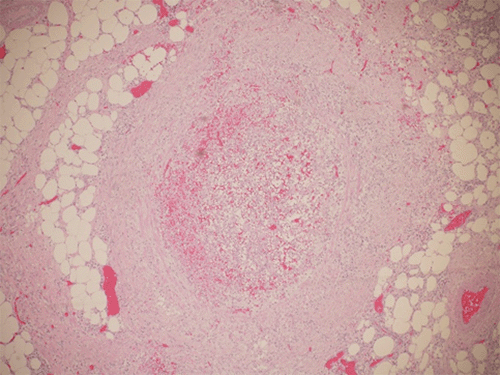

The patient underwent exploratory laparotomy, sigmoidectomy, creation of a Hartmann pouch, and end sigmoid colostomy on hospital day 6. Intraoperative findings included phlebitis of the entire length of the IMV extending from near the ligament of Treitz to the superior hemorrhoidal veins. There was retroperitoneal inflammation extending down to the true pelvis. The surgical pathology report showed a benign sigmoid colon with diverticula, subserosal acute and chronic inflammation, abscess formation, fat necrosis, and endovascular thrombi (Figure 2).

Figure 2. Hematoxylin- and Eosin-Stained Pathology Slides, A) Inferior Mesenteric Vein Thrombus and B) Subserositis. Published with Permission

A) Inferior Mesenteric Vein Thrombus

B) Subserositis